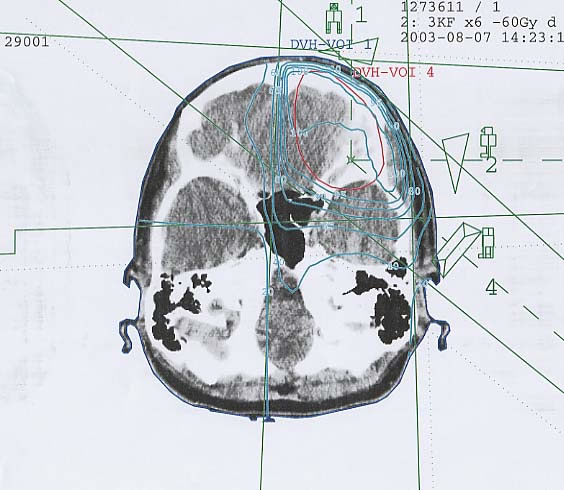

Hirntumore: Bestrahlungsplan

Einführung aktuelle Bilder - Einführung Bestrahlungspläne - Einführung Demonstration